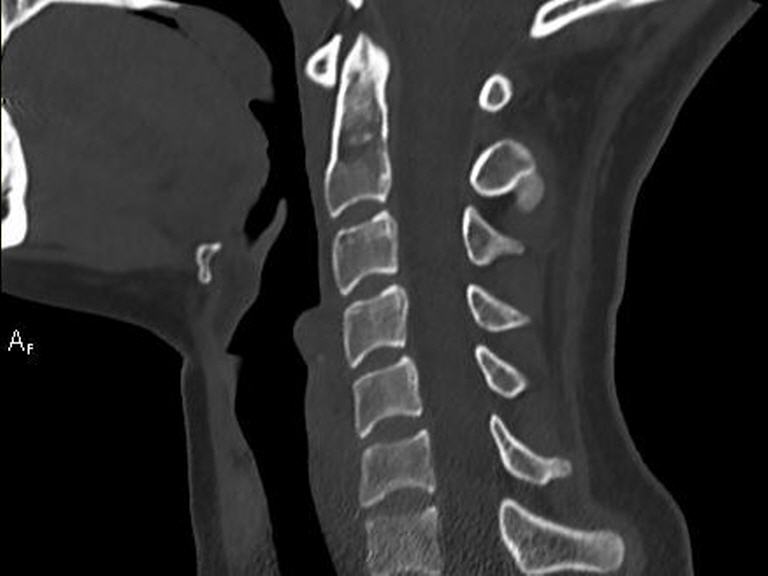

- CTs der Knochen zur Fraktursuche und OP-Vorbereitung